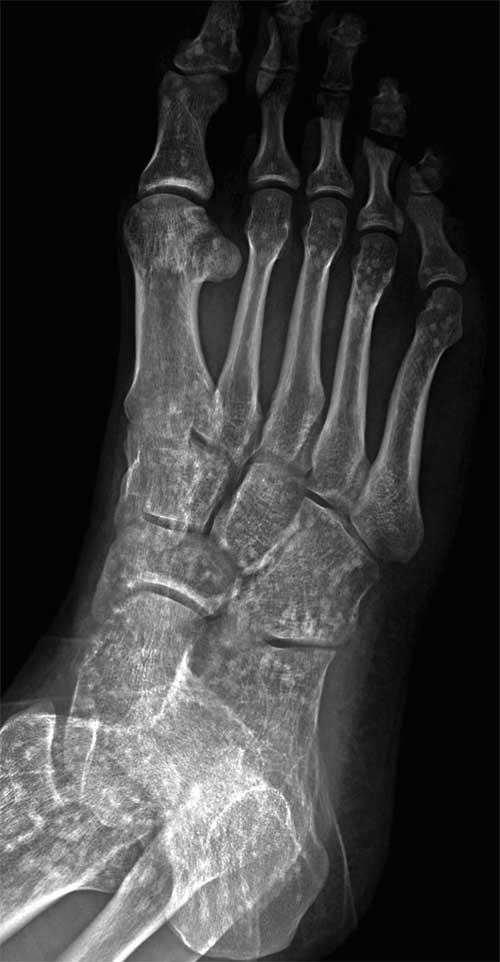

A 21-year-old man presented for evaluation after he sprained his right ankle while hiking. Radiographs showed no fractures but revealed diffuse sclerotic lesions in most of the visualized bones.

A 29-year-old man, an avid runner, presented with a 2½-year history of left midfoot pain on the dorsal area of the first metatarsal-cuneiform joint. The main area of pain appeared to be over the medial dorsal area of the forefoot, around the base of the first metatarsal bone. There was some radiating pain over the first metatarsophalangeal joint but no bruising, swelling, discoloration, skin lesion, temperature change, or obvious deformity.